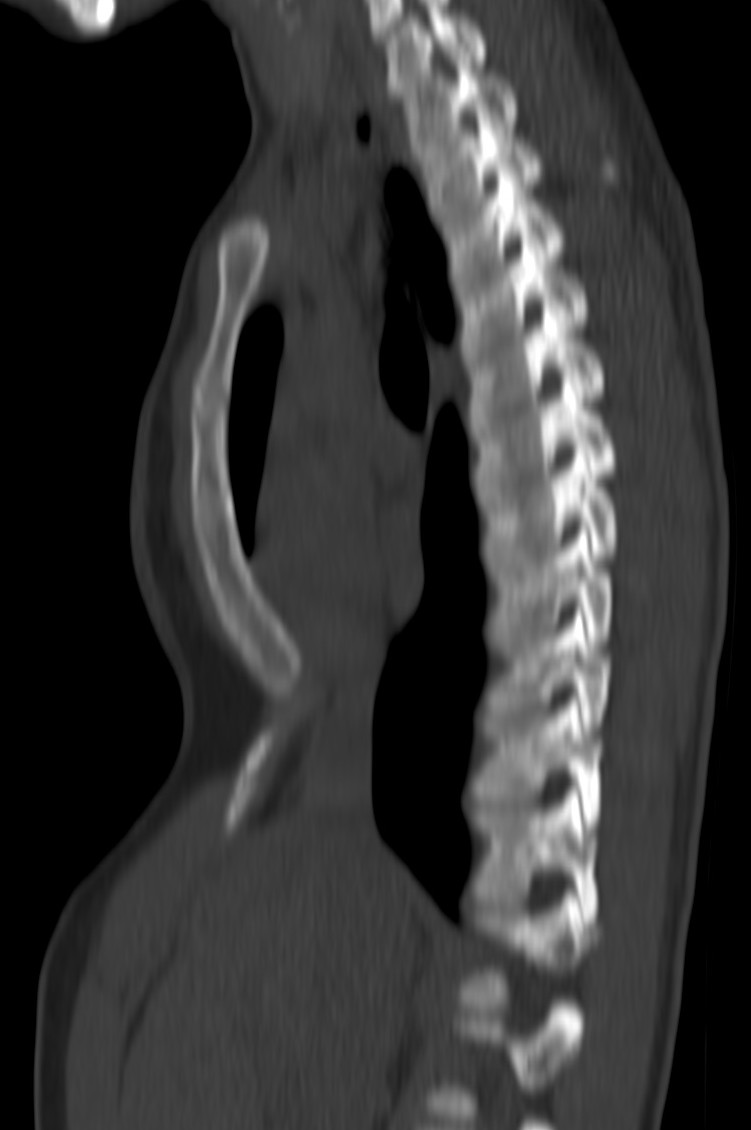

El diagnóstico es clínico. Con la imagen evaluamos mejor la deformidad, útil en caso de ser necesaria la cirugía.

En la Rx de tórax se observa el borramiento del borde cardiaco derecho y en la placa lateral, la depresión interna del esternón, característicamente del cuerpo esternal y de la apófisis xifoides. En casos más acentuados, el corazón, los pulmones, el esófago y el diafragma pueden estar comprimidos, con desplazamiento del corazón hacia la izquierda y prominencia del tronco de la arteria pulmonar en la proyección PA; hallazgos mas evidentes gracias al TC y las reconstrucciones.